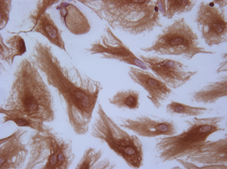

Anche le cellule hanno uno scheletro

Si chiamo citoscheletro e permette alle cellule di muoversi e di modificare la...